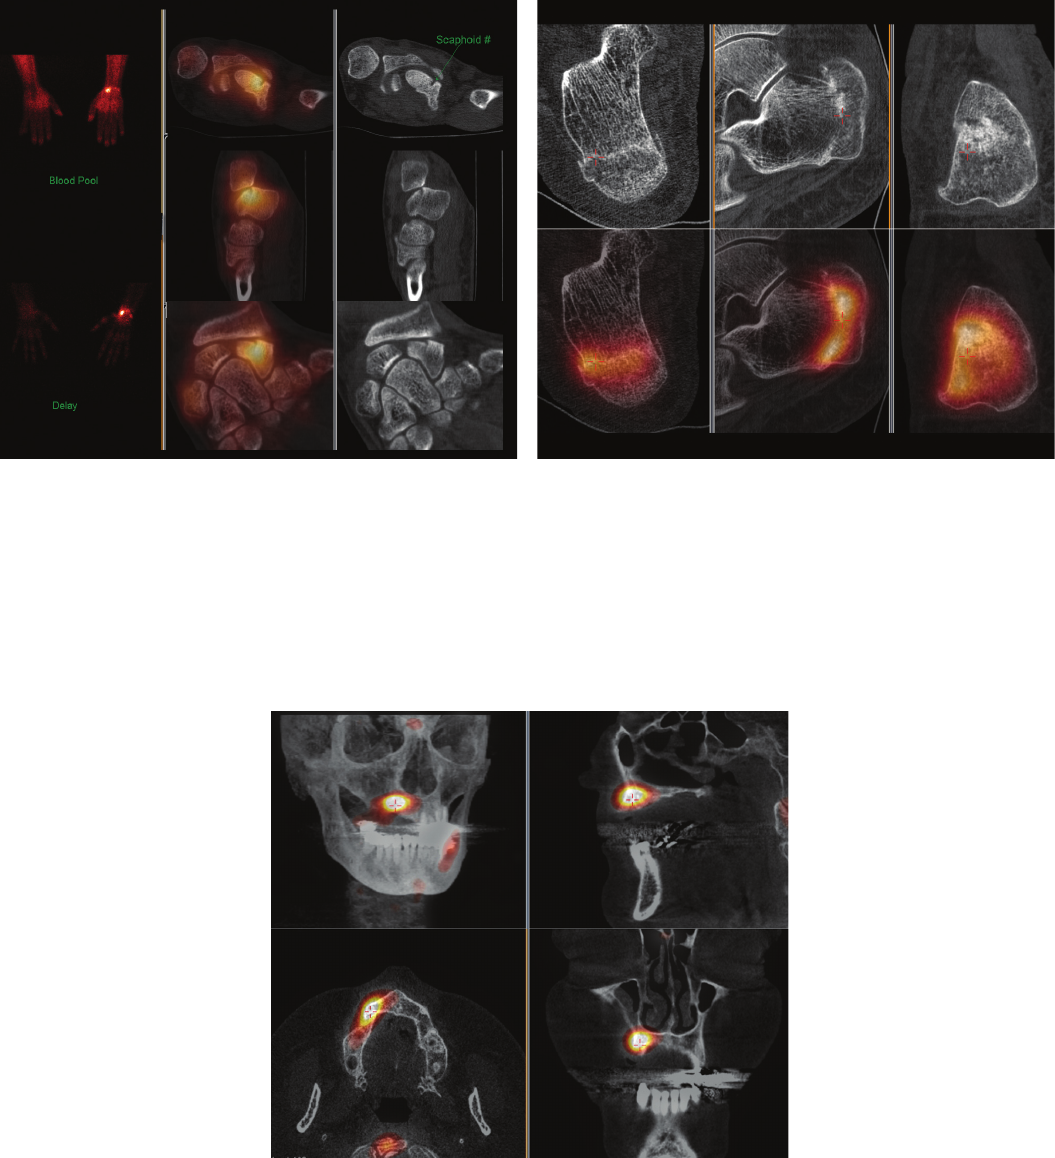

Figure 1 Tc-99m HDP SPECT/CT study performed on an 80-year-old patient with severe

ankle pain and suspected stress fracture. BrightView XCT exam reveals markedly increased

vascularity and delayed uptake in the hind foot and demonstrated intense uptake in right

talonavicular region with severe degenerative change on low dose CT (subarticular cyst

formation, joint narrowing and periarticular sclerosis).

Clinical data courtesy of Sydney X-Ray, Sydney, Australia

Figure 11 Tc-99m MDP SPECT/CT study performed on a 22-year-old male

12 weeks post scaphoid fracture due to continued tenderness. BrightView XCT

study conrmed scaphoid fracture with incomplete union. After more

aggressive orthopedic treatment, fracture healed and patient is symptom-free.

Clinical data courtesy of The Royal Wolverhampton Hospitals NHS Trust, Surrey, UK

Figure 12 Tc-99m HPD SPECT/CT study performed on a patient with

right heel pain for a few months. BrightView XCT study revealed intense

uptake in right calcaneus along a fracture line posteriorly in the CT, which also

demonstrated malalignment and impaction of the fracture. Patient was managed

appropriately for the stress fracture and orthopedic review was arranged to

assess the malalignment of the fracture. No further imaging was required.

Figure 13 Tc-99m DPD SPECT/CT study performed on a 60-year-old

female with metastasis from breast cancer. Patient was imaged with BrightView

XCT one year after bisphosphonate-associated osteonecrosis in the maxilla

region to evaluate for osteomyelitis and to plan for further surgical intervention.

BrightView XCT images provided accurate localization of persistently increased

bone metabolism compatible with osteonecrosis or osteomyelitis in the jaw and

appropriate planning of the extent of surgery to reconstruct the affected area.

Clinical data courtesy of Inselspital Bern University Hospital, Bern, Switzerland